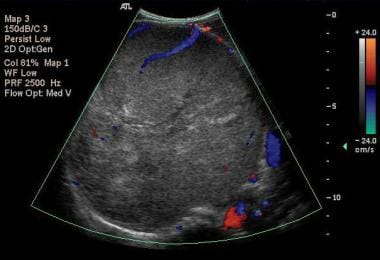

Nutcracker syndrome is the compression of ..

the LEFT renal vein between the SMA and abdominal aorta

What is another name for nutcracker syndrome?

renal vein entrapment

With nutcracker syndrome, the left renal vein will reveal ___ with doppler evaluation

elevated pressure